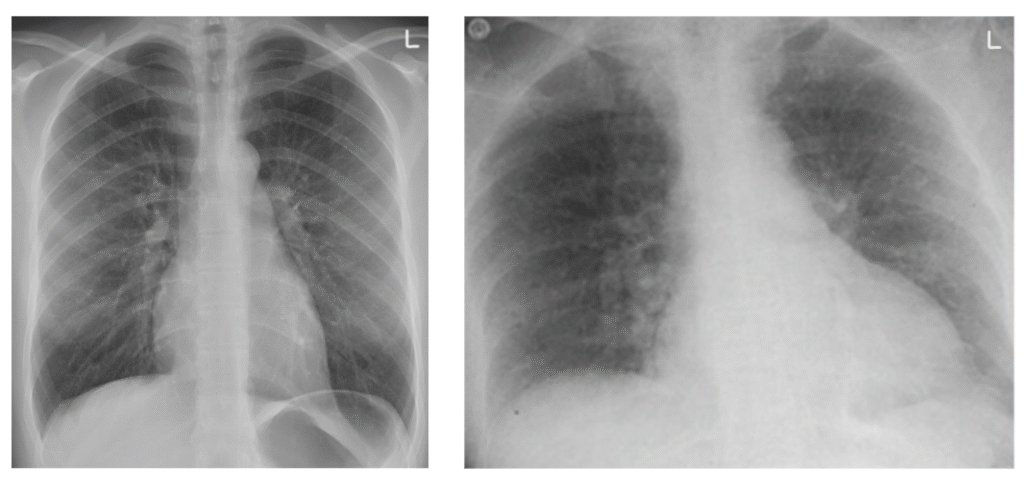

πWe can see below a standard chest xray on the left and on the right, we can observe the effects of shape distortion that has caused our anatomy to seem wider than in reality: